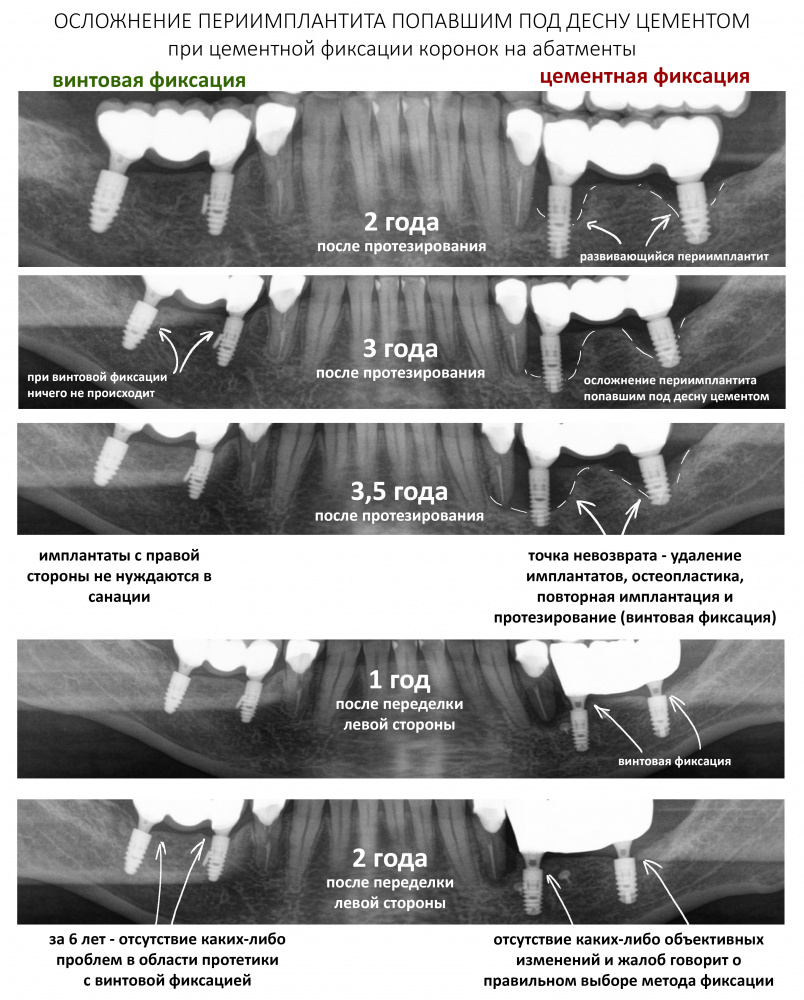

К последним, несомненно, стоит отнести операции имплантации с одновременной костной аугментацией. Те самые случаи, когда мы при установке имплантата наращиваем костную ткань вокруг него.

В отличие от принятого ранее последовательного подхода, проведение остеопластики одновременно с имплантацией позволяет сократить как время, так и травматичность имплантологического лечения, а также в какой-то мере снизить его стоимость.

Это позволило сократить сроки лечения в большинстве случаев до 3-4 месяцев, упростить и удешевить саму стоматологическую реабилитацию.